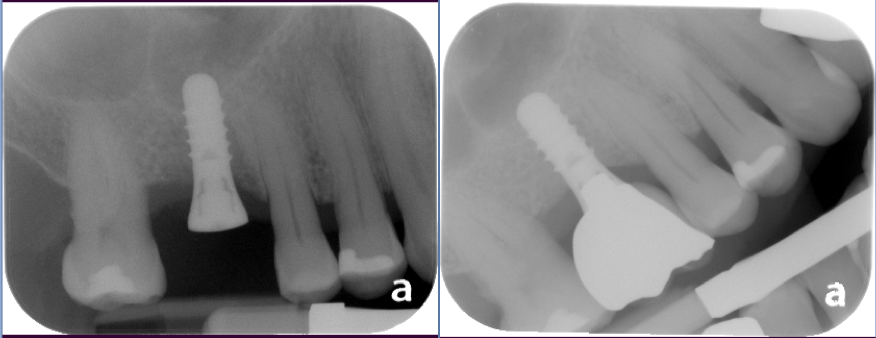

Sinus Lift Implant Vancouver Burnaby Periodontist Implant Dentist IMPreESS Perio

Dental Implant Centre in Vancouver Burnaby Sinus Lift Dental implant Surgery Dr. Noroozi Implant Specialist IMPrESS Perio Implant Center.001

Sinus Lift, Bone Graft, Implants Dr. Noroozi IMPrESS Perio Implant Center